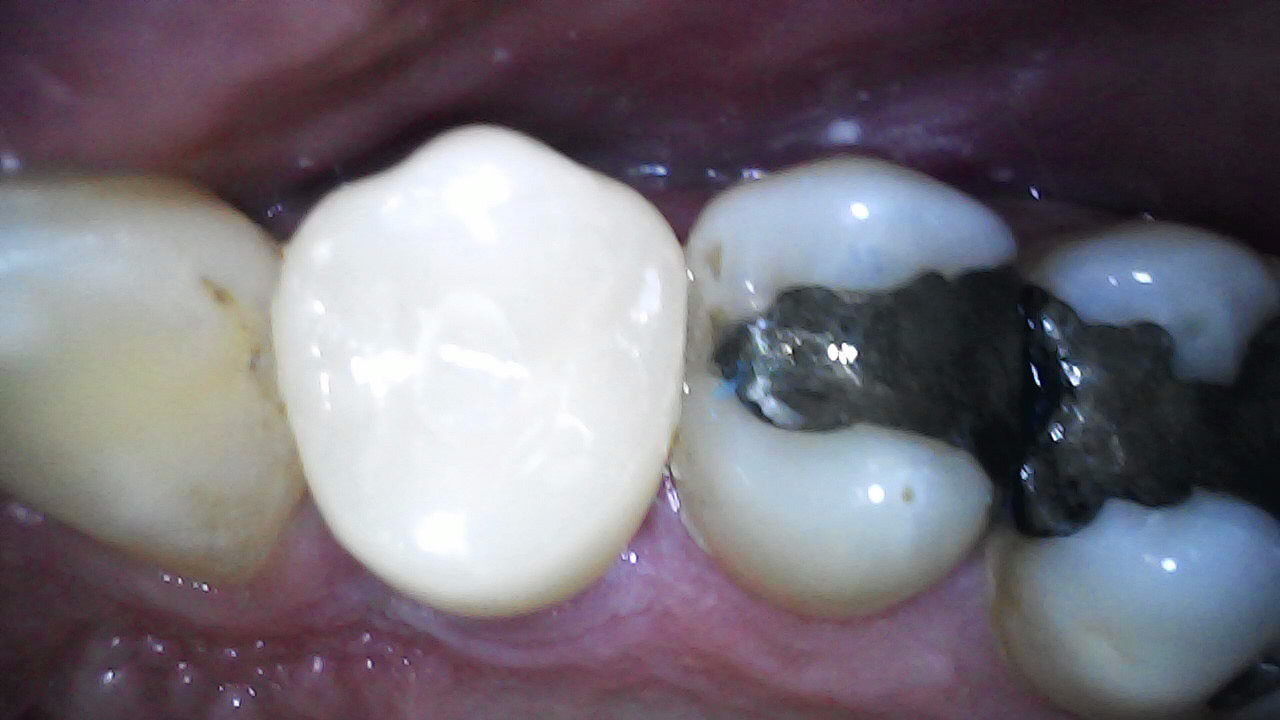

47

INITIAL